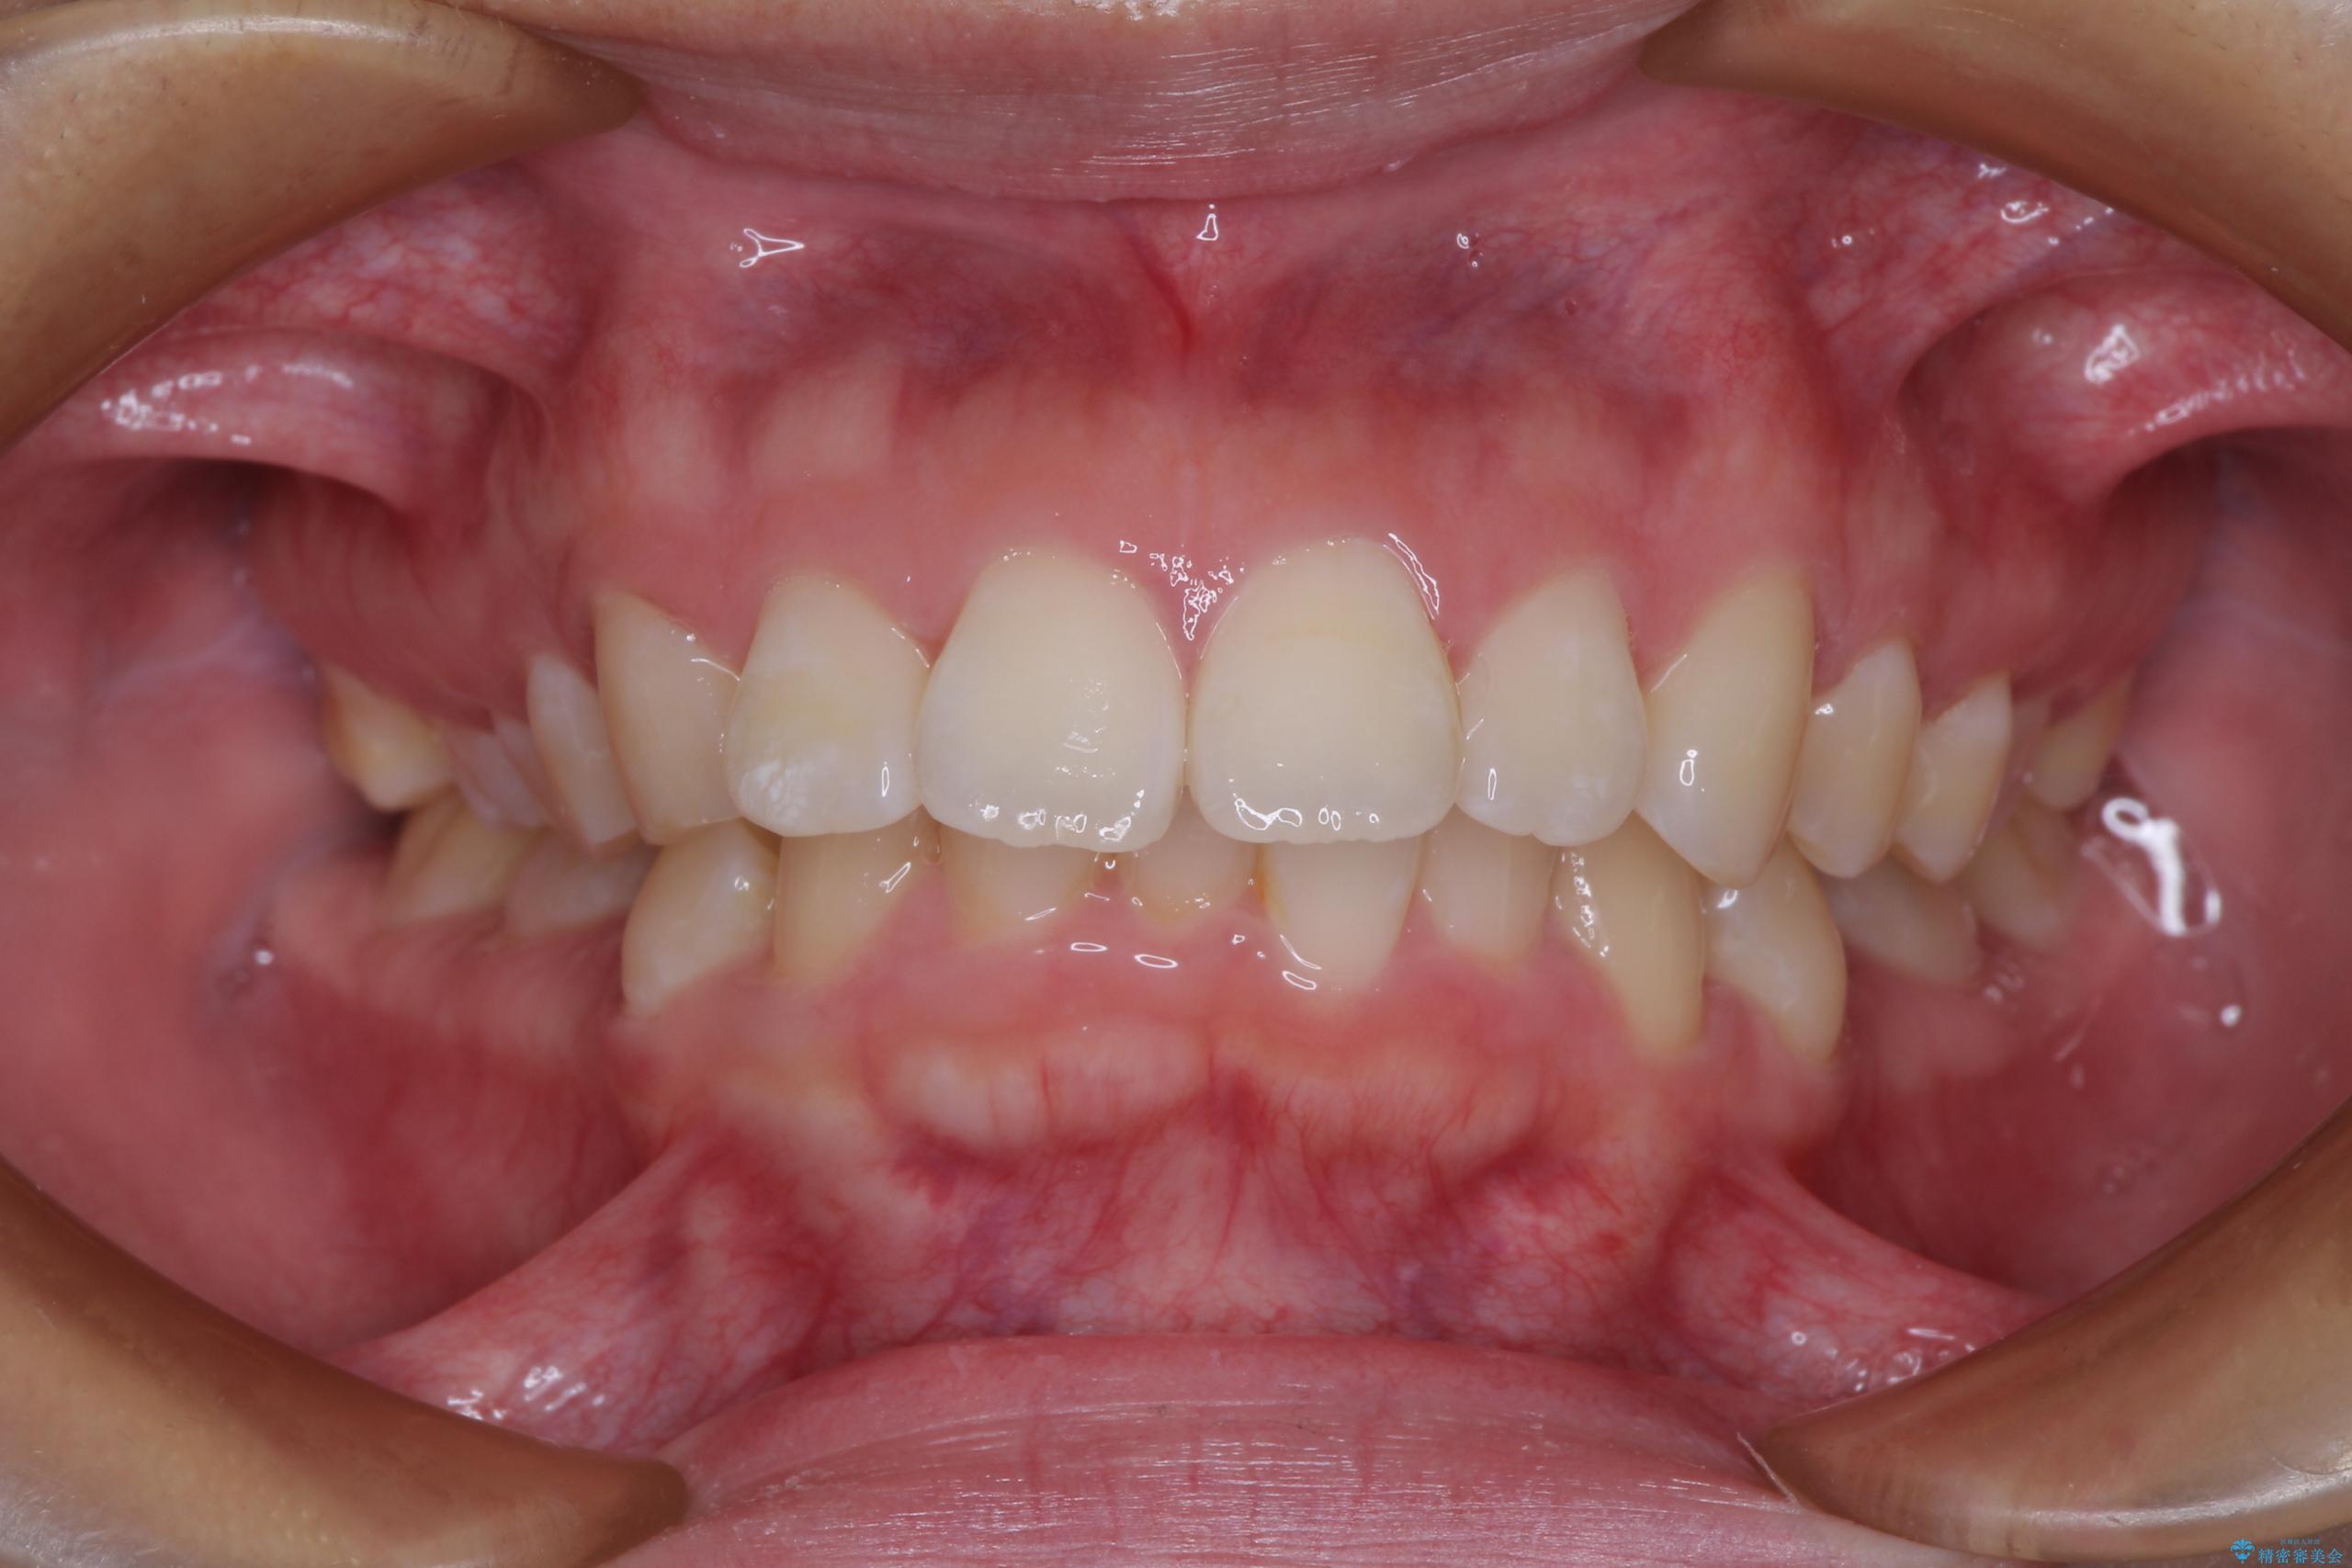

- 上顎前歯が飛び出していて唇がうまく閉じられないとのことで来院された患者様です。

くちばしのように前歯が突出していたため、口元を積極的に引っ込めるために、上下左右の小臼歯4本を抜歯することとしました。

また、上顎歯列が下顎に対して前方位に位置していたため、補助装置を用いて上顎歯列を後方に移動させ、より積極的に口元を下げるようにしました。

上下正中位置を改善するため、左下はイレギュラーに第二小臼歯を抜歯しました。そのため治療期間の長期化が予想されましたが、2年半ほどで期待通りの歯列に仕上げることができました。